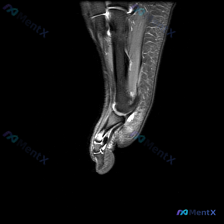

这是踝关节上方水平的轴位T2序列MRI:

- 解剖层面:显示踝穴上方的胫骨远端干骺端、腓骨远端,可清晰识别跟腱、胫骨后肌腱、趾长屈肌腱、踇长屈肌腱、腓骨长短肌腱等结构

- 核心阳性发现:内踝后方胫骨后肌腱的腱鞘区域可见明显异常高信号,提示腱鞘积液;胫骨后肌腱走行区周围软组织可见轻度弥漫性高信号,提示软组织炎症水肿

- 其他表现:腓骨长短肌腱形态信号正常,无明显腱鞘积液;胫骨腓骨骨髓信号均匀,无局灶性水肿或骨质异常信号